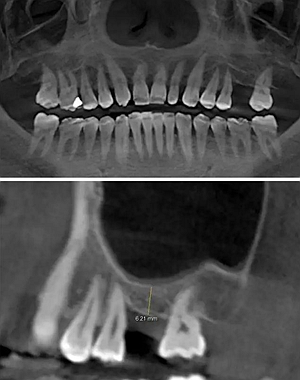

術(shù)前CBCT檢查

骨高度不足,內(nèi)提升的適應(yīng)癥??梢姼]膜致密,厚度均勻。骨高度不足,骨寬度尚可。